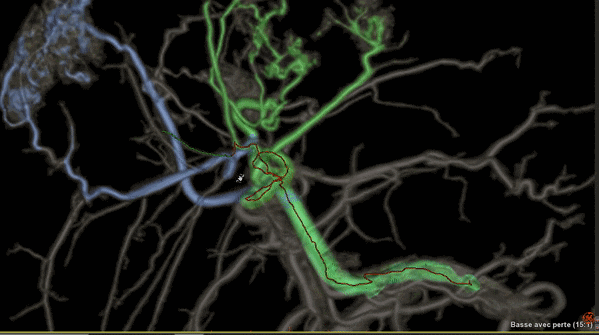

Liver ASSIST V.I,一種增強型軟件

可利用分析工具幫助臨床醫(yī)生克服腫瘤治療的挑戰(zhàn),例如,阻斷肝部腫瘤周邊供養(yǎng)血管是一種有效的介入治療方法,Liver ASSIST V.I可以通過精確高效的血管解剖分析來界定并精準選擇注射點,如同Google地圖一樣進行路徑引導(dǎo),可以術(shù)前進行手術(shù)預(yù)演來提供手術(shù)的精準度,減少手術(shù)并發(fā)癥,讓人工智能的智慧在介入治療中閃光。